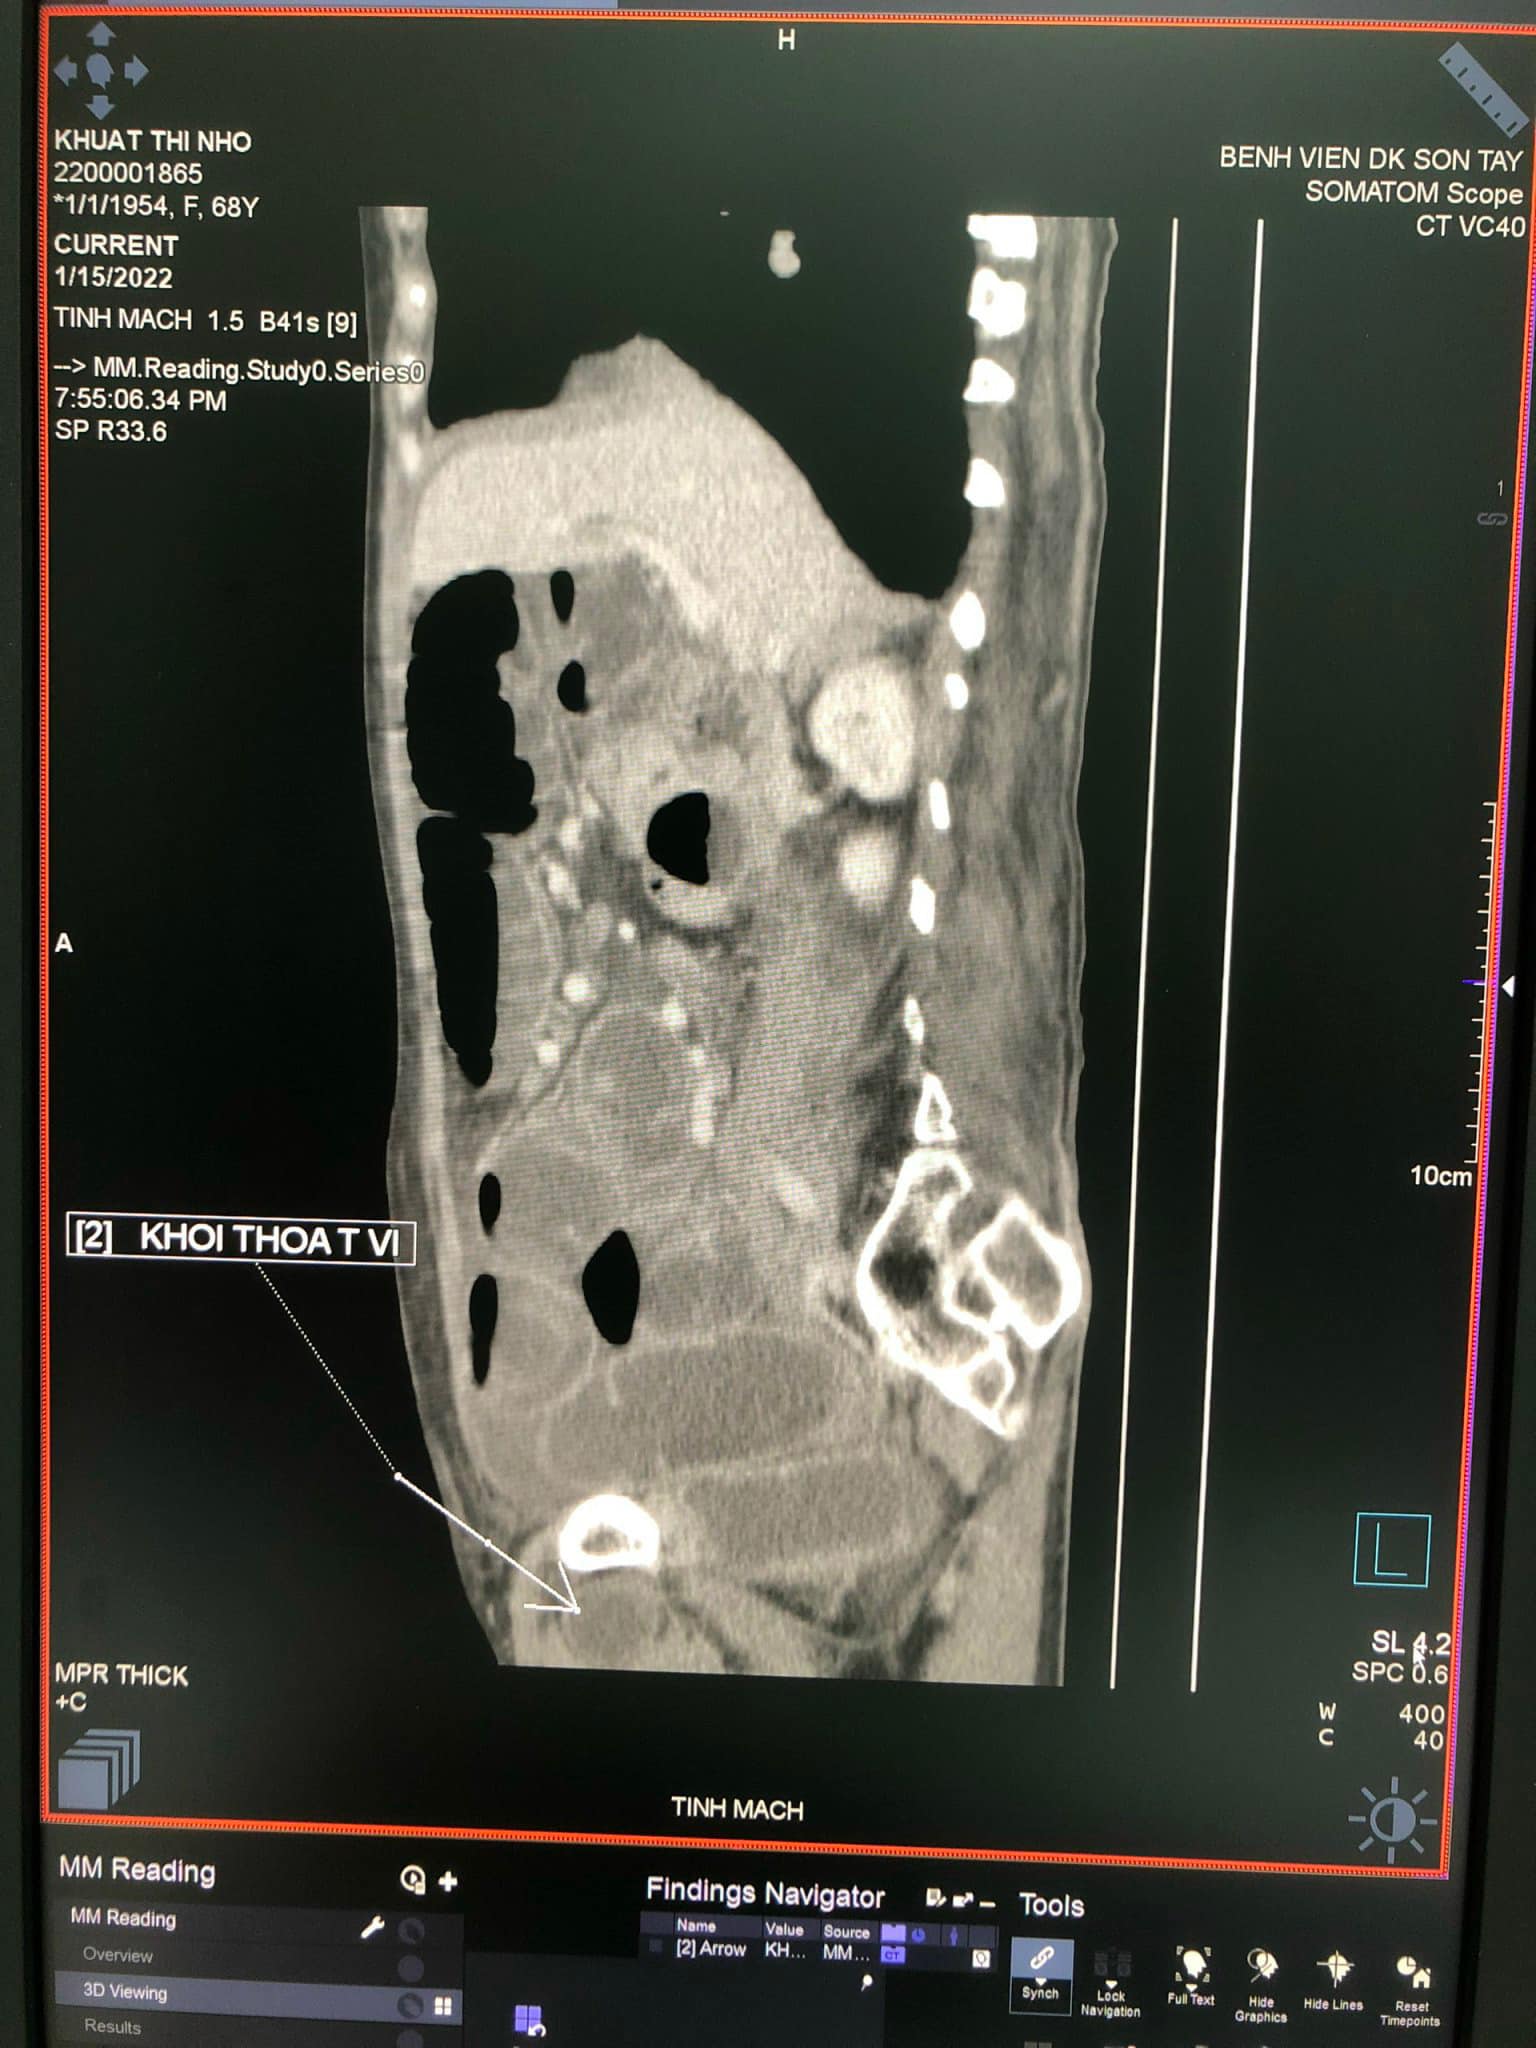

Qua thăm khám, thực hiện chụp cắt lớp vi tính (CT) phát hiện có quai ruột non chui qua và kẹt ở lỗ bịt bên phải, các quai ruột non giãn, đường kính từ 27-30mm. Tiến hành hội chẩn, các bác sĩ xác định bệnh nhân bị thoát vị bịt bên phải nghẹt, chỉ định mổ cấp cứu.

Bệnh nhân Khuất Thị N đã được bác sĩ khoa Ngoại Tổng hợp, khoa Chẩn đoán hình ảnh, khoa Gây mê và Hồi sức cấp cứu Bệnh viện đa khoa Sơn Tây phát hiện và phẫu thuật cấp cứu kịp thời. Quá trình phẫu thuật ghi nhận các quai ruột giãn to, nhiều dịch. Quai ruột cách góc Treizt khoảng 40cm chui vào lỗ bịt bên phải gây hoại tử ruột. Tiến hành giải phóng quai ruột nghẹt, khâu lại lỗ bịt. Cắt đoạn ruột hoại tử, đầu trên cách góc Treizt 20cm xét thấy phải nối ngay không thể làm hậu môn nhân tạo được. Kíp phẫu thuật đã phải nối ruột bên bên luôn.